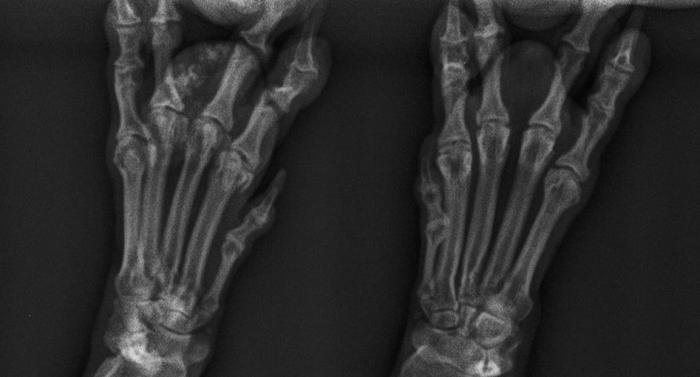

Las radiografías latero-laterales y dorso-ventrales de las extremidades anteriores mostraron material amorfo radiodenso localizado en la almohadilla afectada (Figuras2 y 3). Se realizó citología PAF (Punción con Aguja Fina), analítica sanguínea y biopsia de la zona. El análisis hematológico evidenció hiperfosfatemia leve, sin alteraciones en calcio, función renal o hepática.